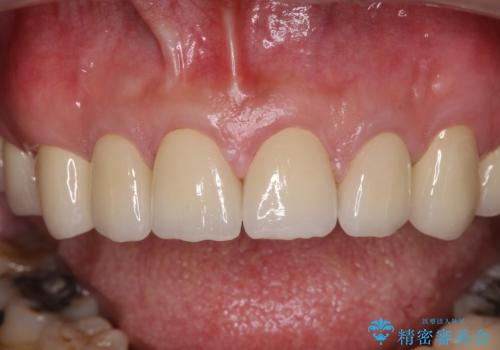

当初は前歯6歯をオールセラミッククラウンで補綴する予定でしたが、前歯が綺麗に仕上がったことで、奥歯まで延長して補綴することとしました。

黄ばんだ前歯や白すぎたクラウン、プラスチックの継ぎ接ぎなどを全てオールセラミッククラウンの統一感のある前歯に仕上げました。